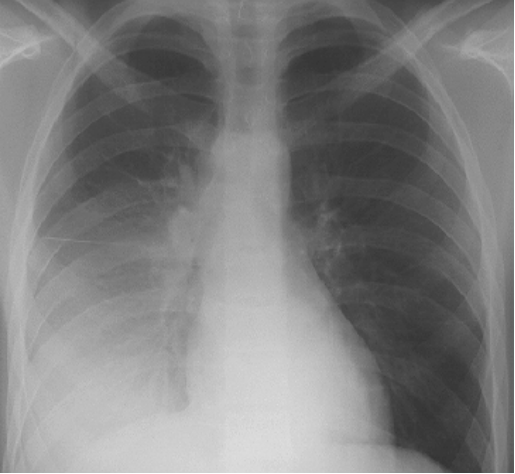

13个小时前后胸片对照

金黄色葡萄球菌性肺炎

(staphylococcal pneumonia)

一、起病急,病情严重,发展迅速

二、毒血症状明显,如高热、面色苍白、气促 、纳 呆、腹胀等,可有腥红热样或荨麻疹样皮疹

三、易形成脓胸、脓气胸、肺大泡、纵隔气肿、皮下气肿等并发症,易变性是金葡菌的X线特征